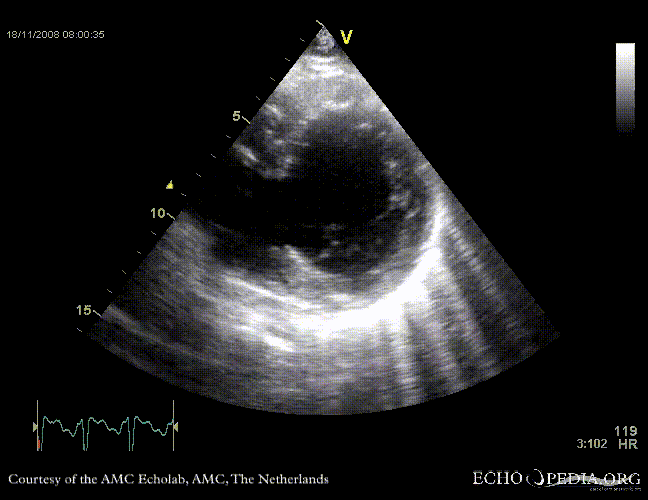

Rupture of the ventricular septum

VSR 1